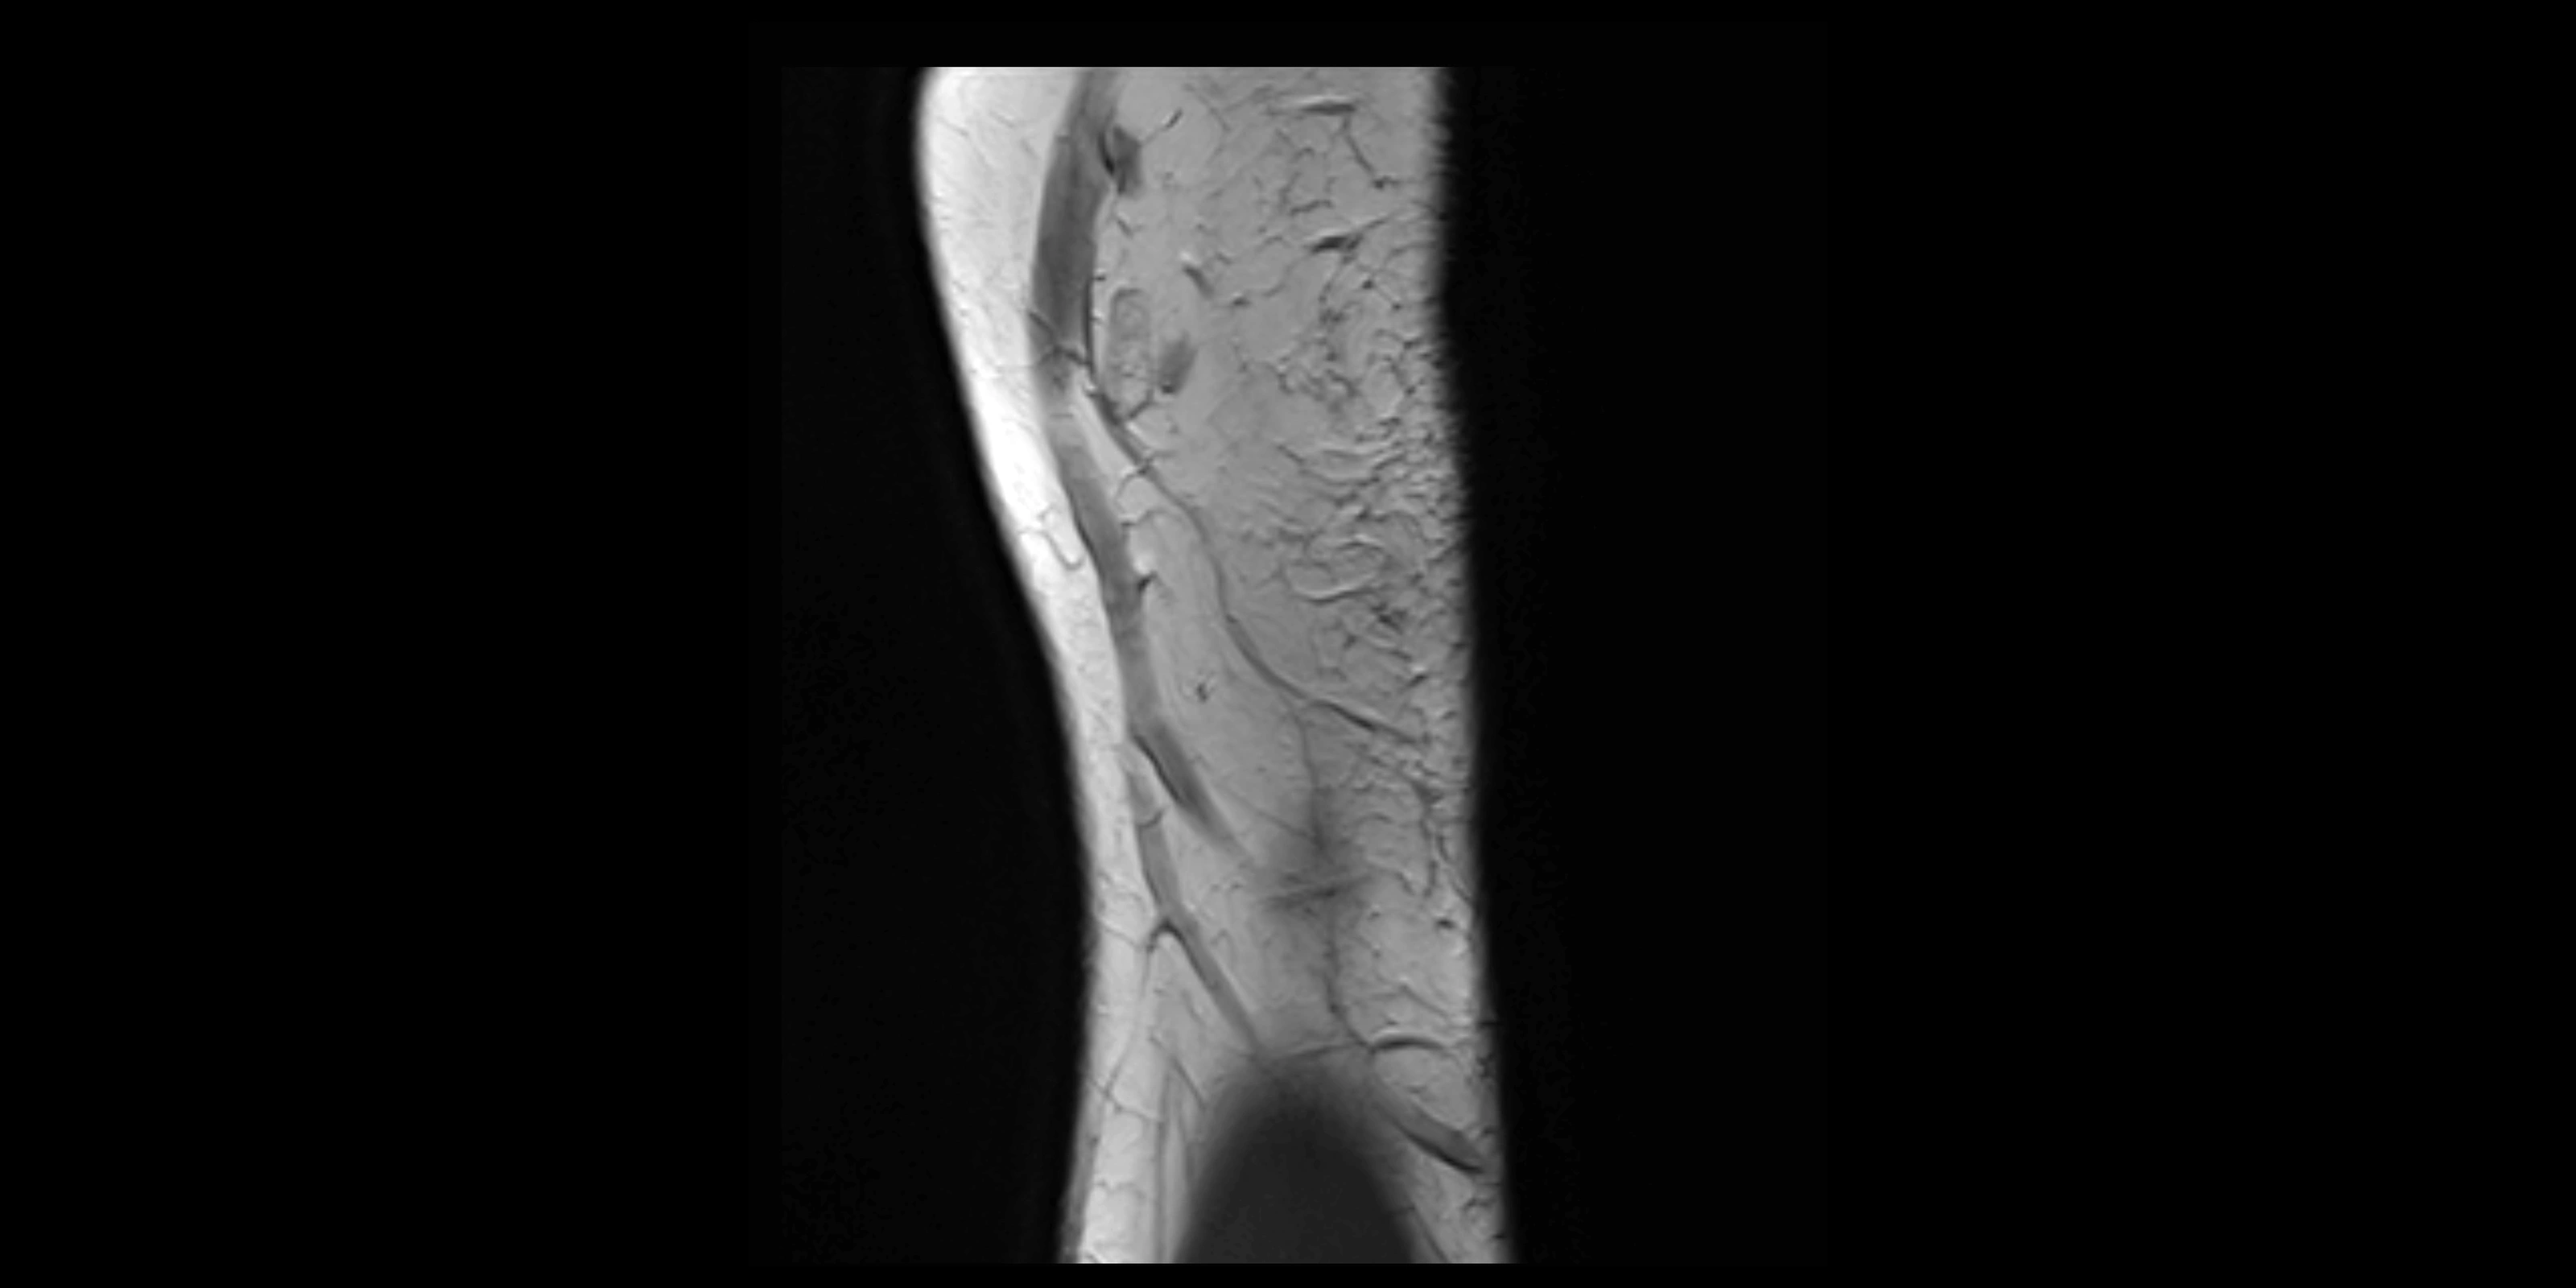

MRI Appearance

T1-weighted images:

• Ligament: low signal intensity (dark), appearing as a continuous band around the radial head.

• Adjacent fat and marrow: bright, creating contrast with the ligament.

• Thickening or disruption indicates injury or fibrosis.

• Joint capsule and synovium seen as thin low-signal lines contiguous with ligament margins.

T2-weighted images:

• Ligament: low signal (dark) with clear delineation from joint fluid.

• Fluid or edema: bright hyperintense, separating or surrounding the ligament in partial tears.

• Complete tear: discontinuity or non-visualization of ligament fibers, often with joint effusion.

STIR:

• Normal ligament: dark band encircling radial head.

• Pathology: bright hyperintense periligamentous signal suggesting edema, sprain, or partial tear.

Proton Density Fat-Saturated (PD FS):

• Normal: dark, well-defined band outlining the radial head.

• Partial tear: irregular or bright hyperintense signal within or adjacent to ligament fibers.

• Joint effusion and reactive synovitis appear bright and are well visualized.

MRI Arthrogram Appearance

• Contrast outlines the proximal radioulnar joint and radial head recess.

• Normal ligament appears as a dark ring surrounding the radial head, containing the injected contrast within the joint cavity.

• Partial tear: contrast extends along the ligament or beneath its fibers.

• Complete tear or subluxation: contrast extravasates around the radial head or ulna, indicating discontinuity.

• Detects capsular defects, instability, or synovial invagination with high sensitivity.